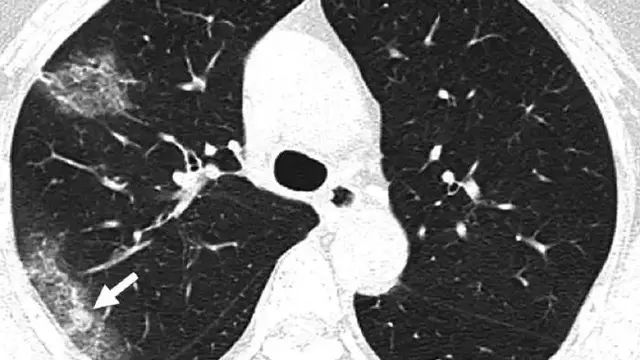

Dilansir dari Dream.co.id, pada Ilmu Kedokteran Radiologi, pemerintah Provinsi Hubei menggunakan teknik yang dikenal dengan istilah Ground-glass opacity (GGO). GGO ini merupakan Teknik CT Scan yang digunakan untuk tes virus corona.

Menggunakan metode GGO ini, membuat para dokter lebih cepat mendiagnosa suatu virus. Termasuk virus COVID-19. Agar pasien bisa lebih cepat ditangani dan disembuhkan.

Teknik Ground-glass opacity dianggap kurang akurat. Sebenarnya melakukan tes dengan tes darah, hasilnya akan lebih akurat. Tetapi para dokter di Wuhan tetap menggunakan teknik GGO ini.

Dokter memiliki alasan khusus untuk menggunakan teknik GGO ini. Karena tenaga kesehatan di rumah sakit kehabisan alat pelindung diri atau APD. Kalau tenaga medis melakukan tes darah, harus menggunakan alat pelindung yang lengkap. Karena mengambil sampel darah merupakan hal rawan terkena virus corona.

Seorang pasien yang didiagnosis suspect COVID-19, akan melakukan tes dengan CT scan. Kemudian hasil scan akan dilihat pada bagian paru-paru. Jika orang tersebut positif, maka pada bagian paru-parunya akan nampak bercak-bercak putih. Bercak ini membentuk ground-glass dan berjumlah banyak.

Jika dilihat melalui CT Scan, paru-paru pada orang normal dan sehat, memiliki ciri-ciri berwarna hitam.

Menurut Paras Lakhani, yang merupakan ahli radiologi di Universitas Thomas Jefferson, bercak-bercak putih pada paru-paru pasien belum pasti karena terinfeksi virus Covid-2019.

Bercak-bercak tersebut bisa menunjukkan banyak jenis infeksi, bakteri, virus dan tanda penyakit tidak menular. Bercak-bercak putih yang wajib diwaspadai adalah bercak yang meluas ke tepi paru-paru.